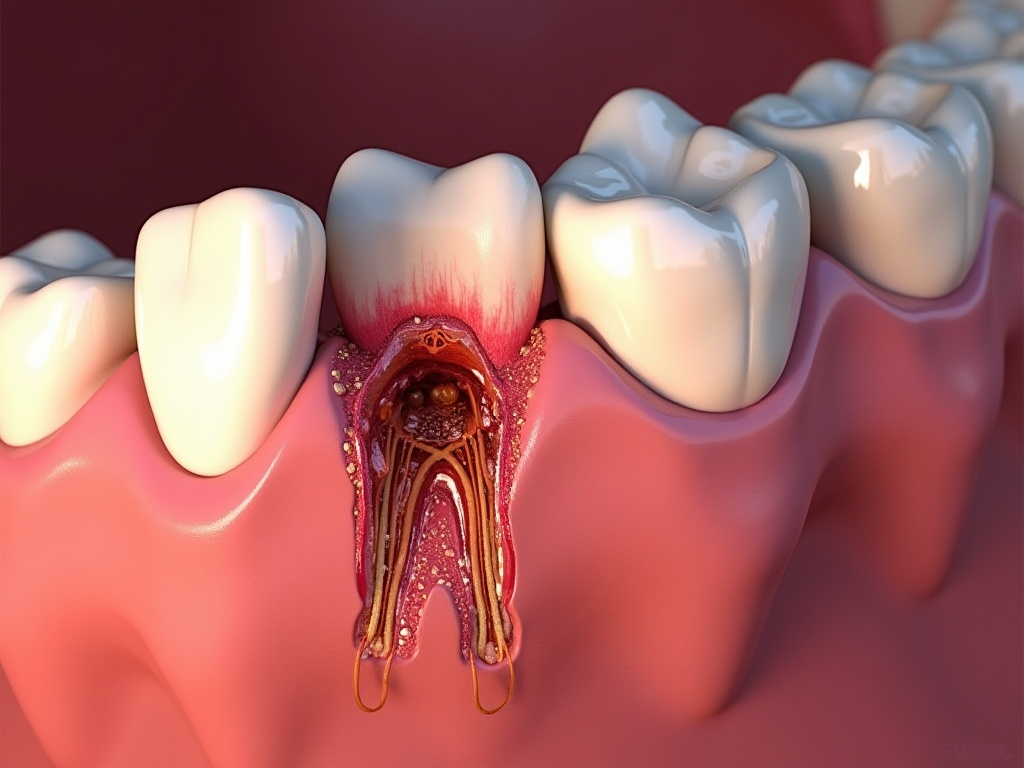

사랑니 근처에는 신경이 있어요!

사랑니 뿌리근처에는 아래턱 신경이라는 커다란 신경이 지나갑니다. 개인마다 다르지만 뽑는 과정에서 신경에 손상을 일으킬 가능성이 있습니다. 신경손상 가능성에 대한 사전 분석이 필요하며 손상 가능성이 있다고 판단되는 경우 경험 많은 의사에게 조심스러운 발치 및 후 처리가 요구됩니다.